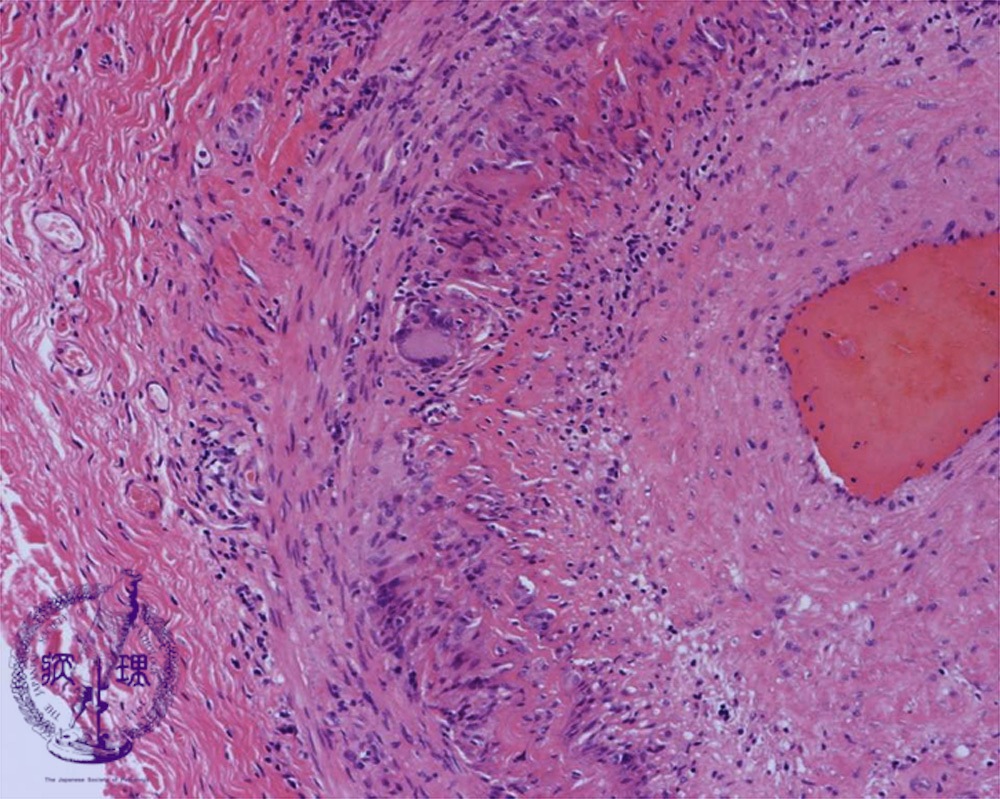

- (14)Giant cell arteritis

Microscopic image (HE, intermediate power view): Infiltration of foreign body type multinucleated giant cells with destruction of the medial elastic laminae is observed.